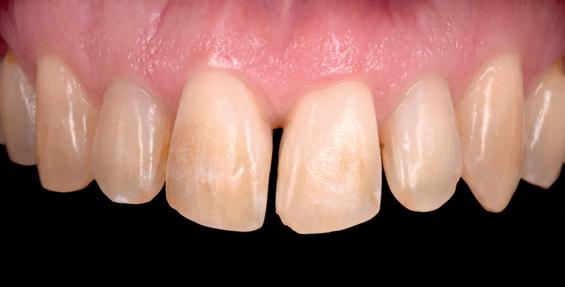

Case 1: Anterior tooth restoration with composite

Restorations with BEAUTIFIL II LS, BEAUTIFIL Flow Plus X and OneGloss by Erik-Jan Muts, M.Sc., Netherlands